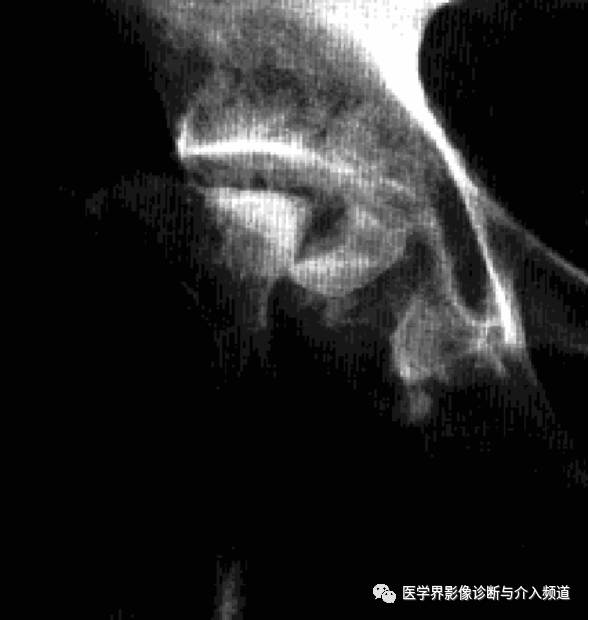

Charcot髋关节病

Charcot髋关节病,又称夏科关节、神经营养性髋关节病,是在中枢性或周围神经性疾病所致的髋关节深部感觉障碍基础上,因反复多次关节外伤继发引起的髋关节病变。常见原因多见于脊髓痨和脊髓空洞症,麻风、糖尿病、周围神经损伤、脊䯝肿瘤等疾病也可伴发。

临床表现:病程长,多单侧受累,有外伤诱因,关节肿大,疼痛不明显,痛觉消失,深反射消失。

影像诊断:首先X线平片。

1、平片:早期关节内积液、软组织肿胀、关节间隙增宽;进展期股骨头关节面变平、关节内游离体,关节旁钙化及骨化,关节脱位;晚期骨端破坏、大量骨赘形成,反应性骨膜增生。

2、CT:早期髋关节积液,周围软组织水肿;随病情进展,骨端增生硬化,边缘骨赘形成,游离体;后期,骨端崩解,关节正常结构破坏,关节腔大量坏死骨块和钙化的软骨碎屑,周围软组织骨化、钙化,增强显示关节囊及滑膜囊明显强化、呈绒毛状突向关节腔。

3、MRI:早期关节积液,软骨变性、破坏,继而关节软骨碎裂、形成游离体,软骨下骨增生硬化、骨赘形成;最终骨赘断裂、骨端碎裂、关节结构消失,骨残端无明显水肿和骨髓浸润征象。增强显示关节囊及滑膜囊明显强化、呈绒毛状突向关节腔,骨残端无明显强化。